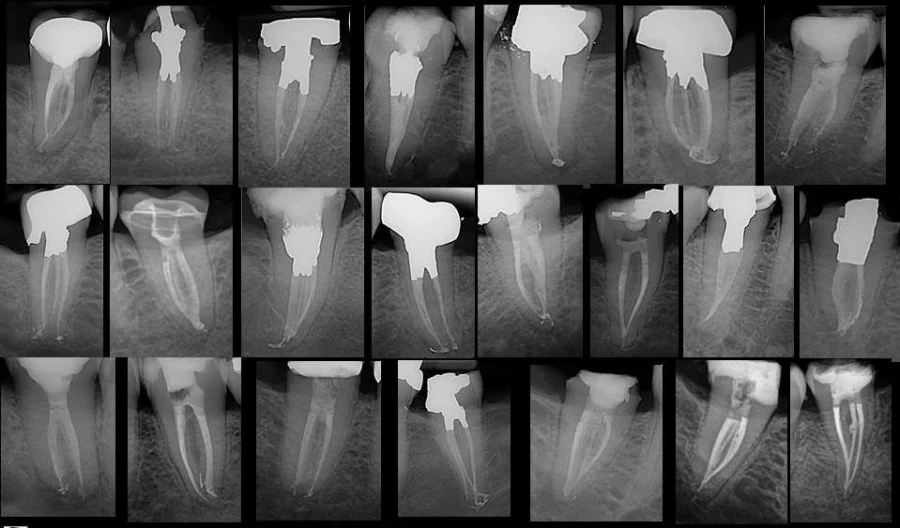

Đọc tiếp- Mục tiêu chính của việc điều trị tủy là tạo dạng, làm sạch tất cả các khoảng không bên…